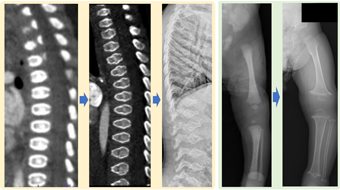

Osteogenesis imperfecta: pathogenesis, classification, and treatment もっと読む

Osteogenesis imperfecta (OI) is a congenital skeletal disorder characterized by varying degrees of bone fragility and deformities. (A) fracture of bilateral humeri in a neonate with OI caused by a pathogenic variant in the COL1A1 gene, (B) calcification of the interosseous membrane in a patient with type 5 OI caused by a specific pathogenic variant, c.-14C>T, in the IFITM5 gene. (C) Mechanism of type I collagen synthesis. Many genes involved in this process have been identified as causative factors of OI, such as the type 1 collagen gene and genes involved in folding (P3H1, CRTAP, and PPIB), collagen processing and crosslinking of type I collagen molecules (SERPINH1, FKBP10, PLOD2, and BMP1), osteoblast differentiation (SP7, TMEM38B, WNT1, CREB3L1, SPARC, and MBTPS2), and bone mineralization (IFITM5 and SERPINF1). ADAMTS-2, a disintegrin and metalloproteinase with thrombospondin motifs 2; BRIL, bone-restricted Ifitm-like; BMP1, bone morphogenetic protein; FKBP65, 65-kDa FK506-binding protein; HSP47, heat shock protein 47; KDELR2, KDEL endoplasmic reticulum protein retention receptor 2; P3H, Prolyl 3-hydroxylase; P4H, prolyl 4-hydroxylase; PEDF, pigment epithelium-derived factor; PICP, carboxyterminal propeptides of type I collagen; PINP, aminoterminal propeptides of type I collagen; SPARC, secreted protein acidic and rich in cysteine.